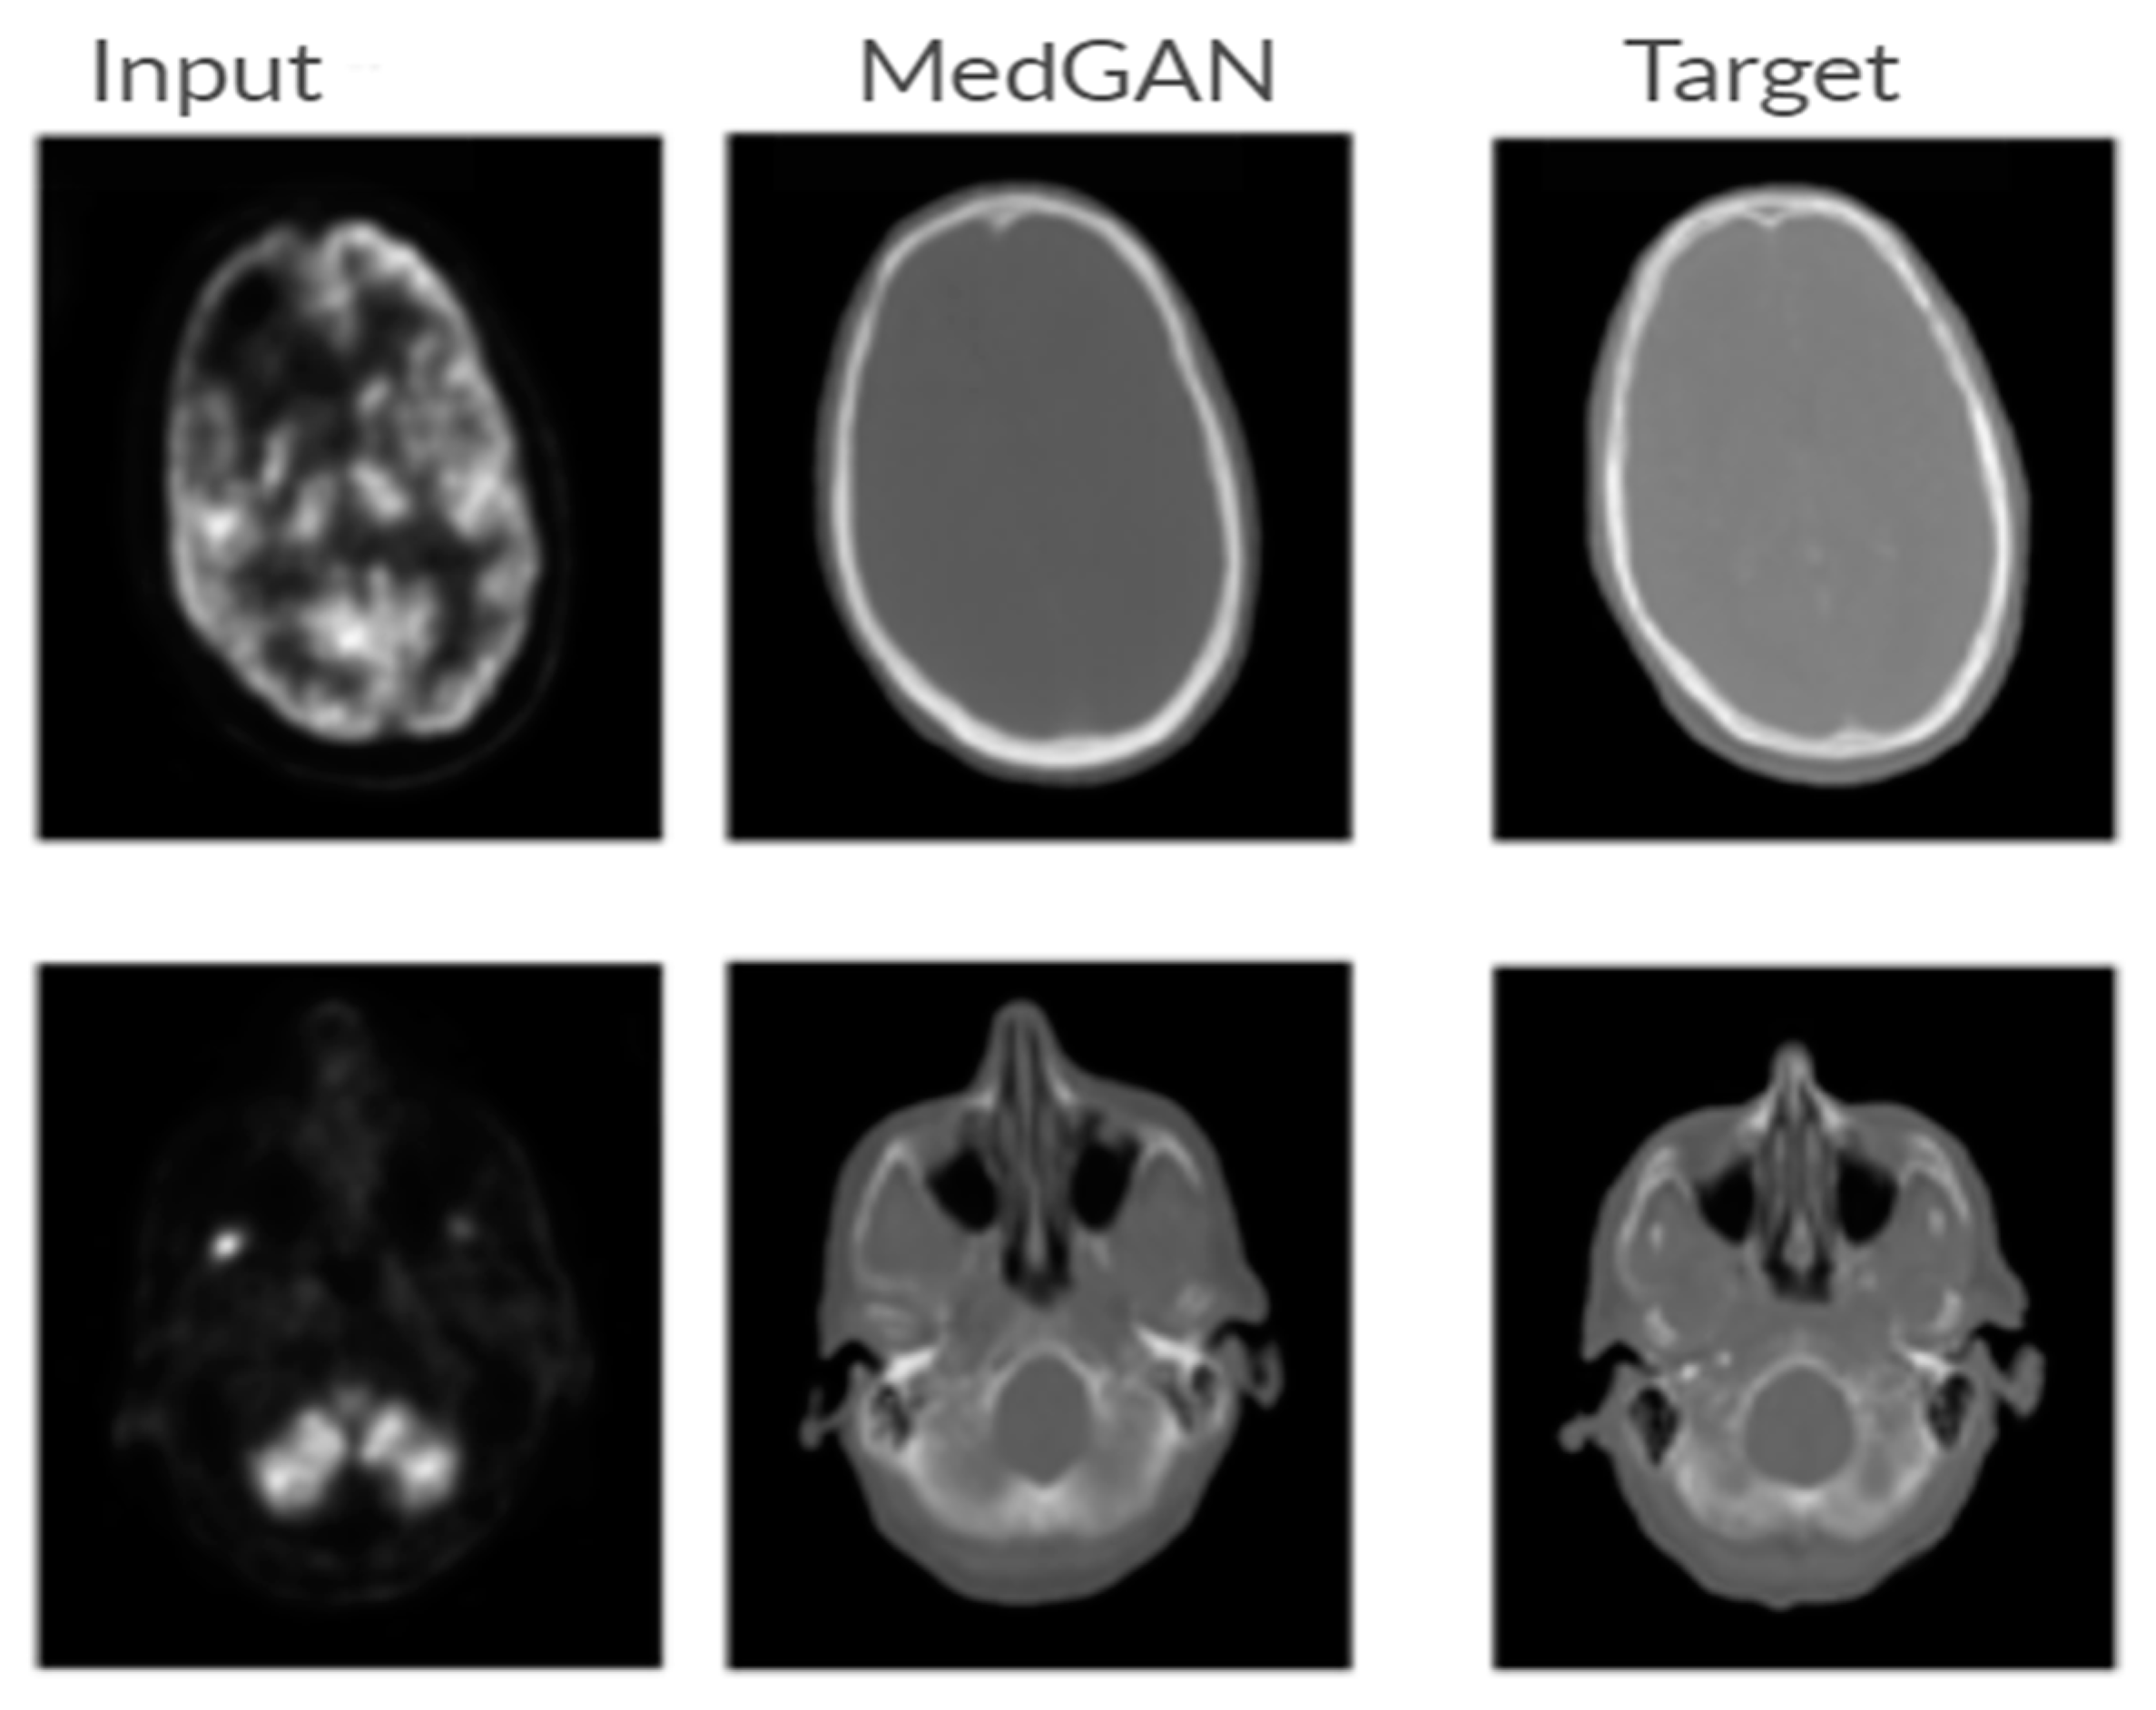

7.3.4. Medical Imaging

- Armanious, K.; Jiang, C.; Fischer, M.; Küstner, T.; Hepp, T.; Nikolaou, K.; Gatidis, S.; Yang, B. MedGAN: Medical image translation using GANs. Comput. Med. Imaging Graph. 2020, 79, 101684. [Google Scholar] [CrossRef]